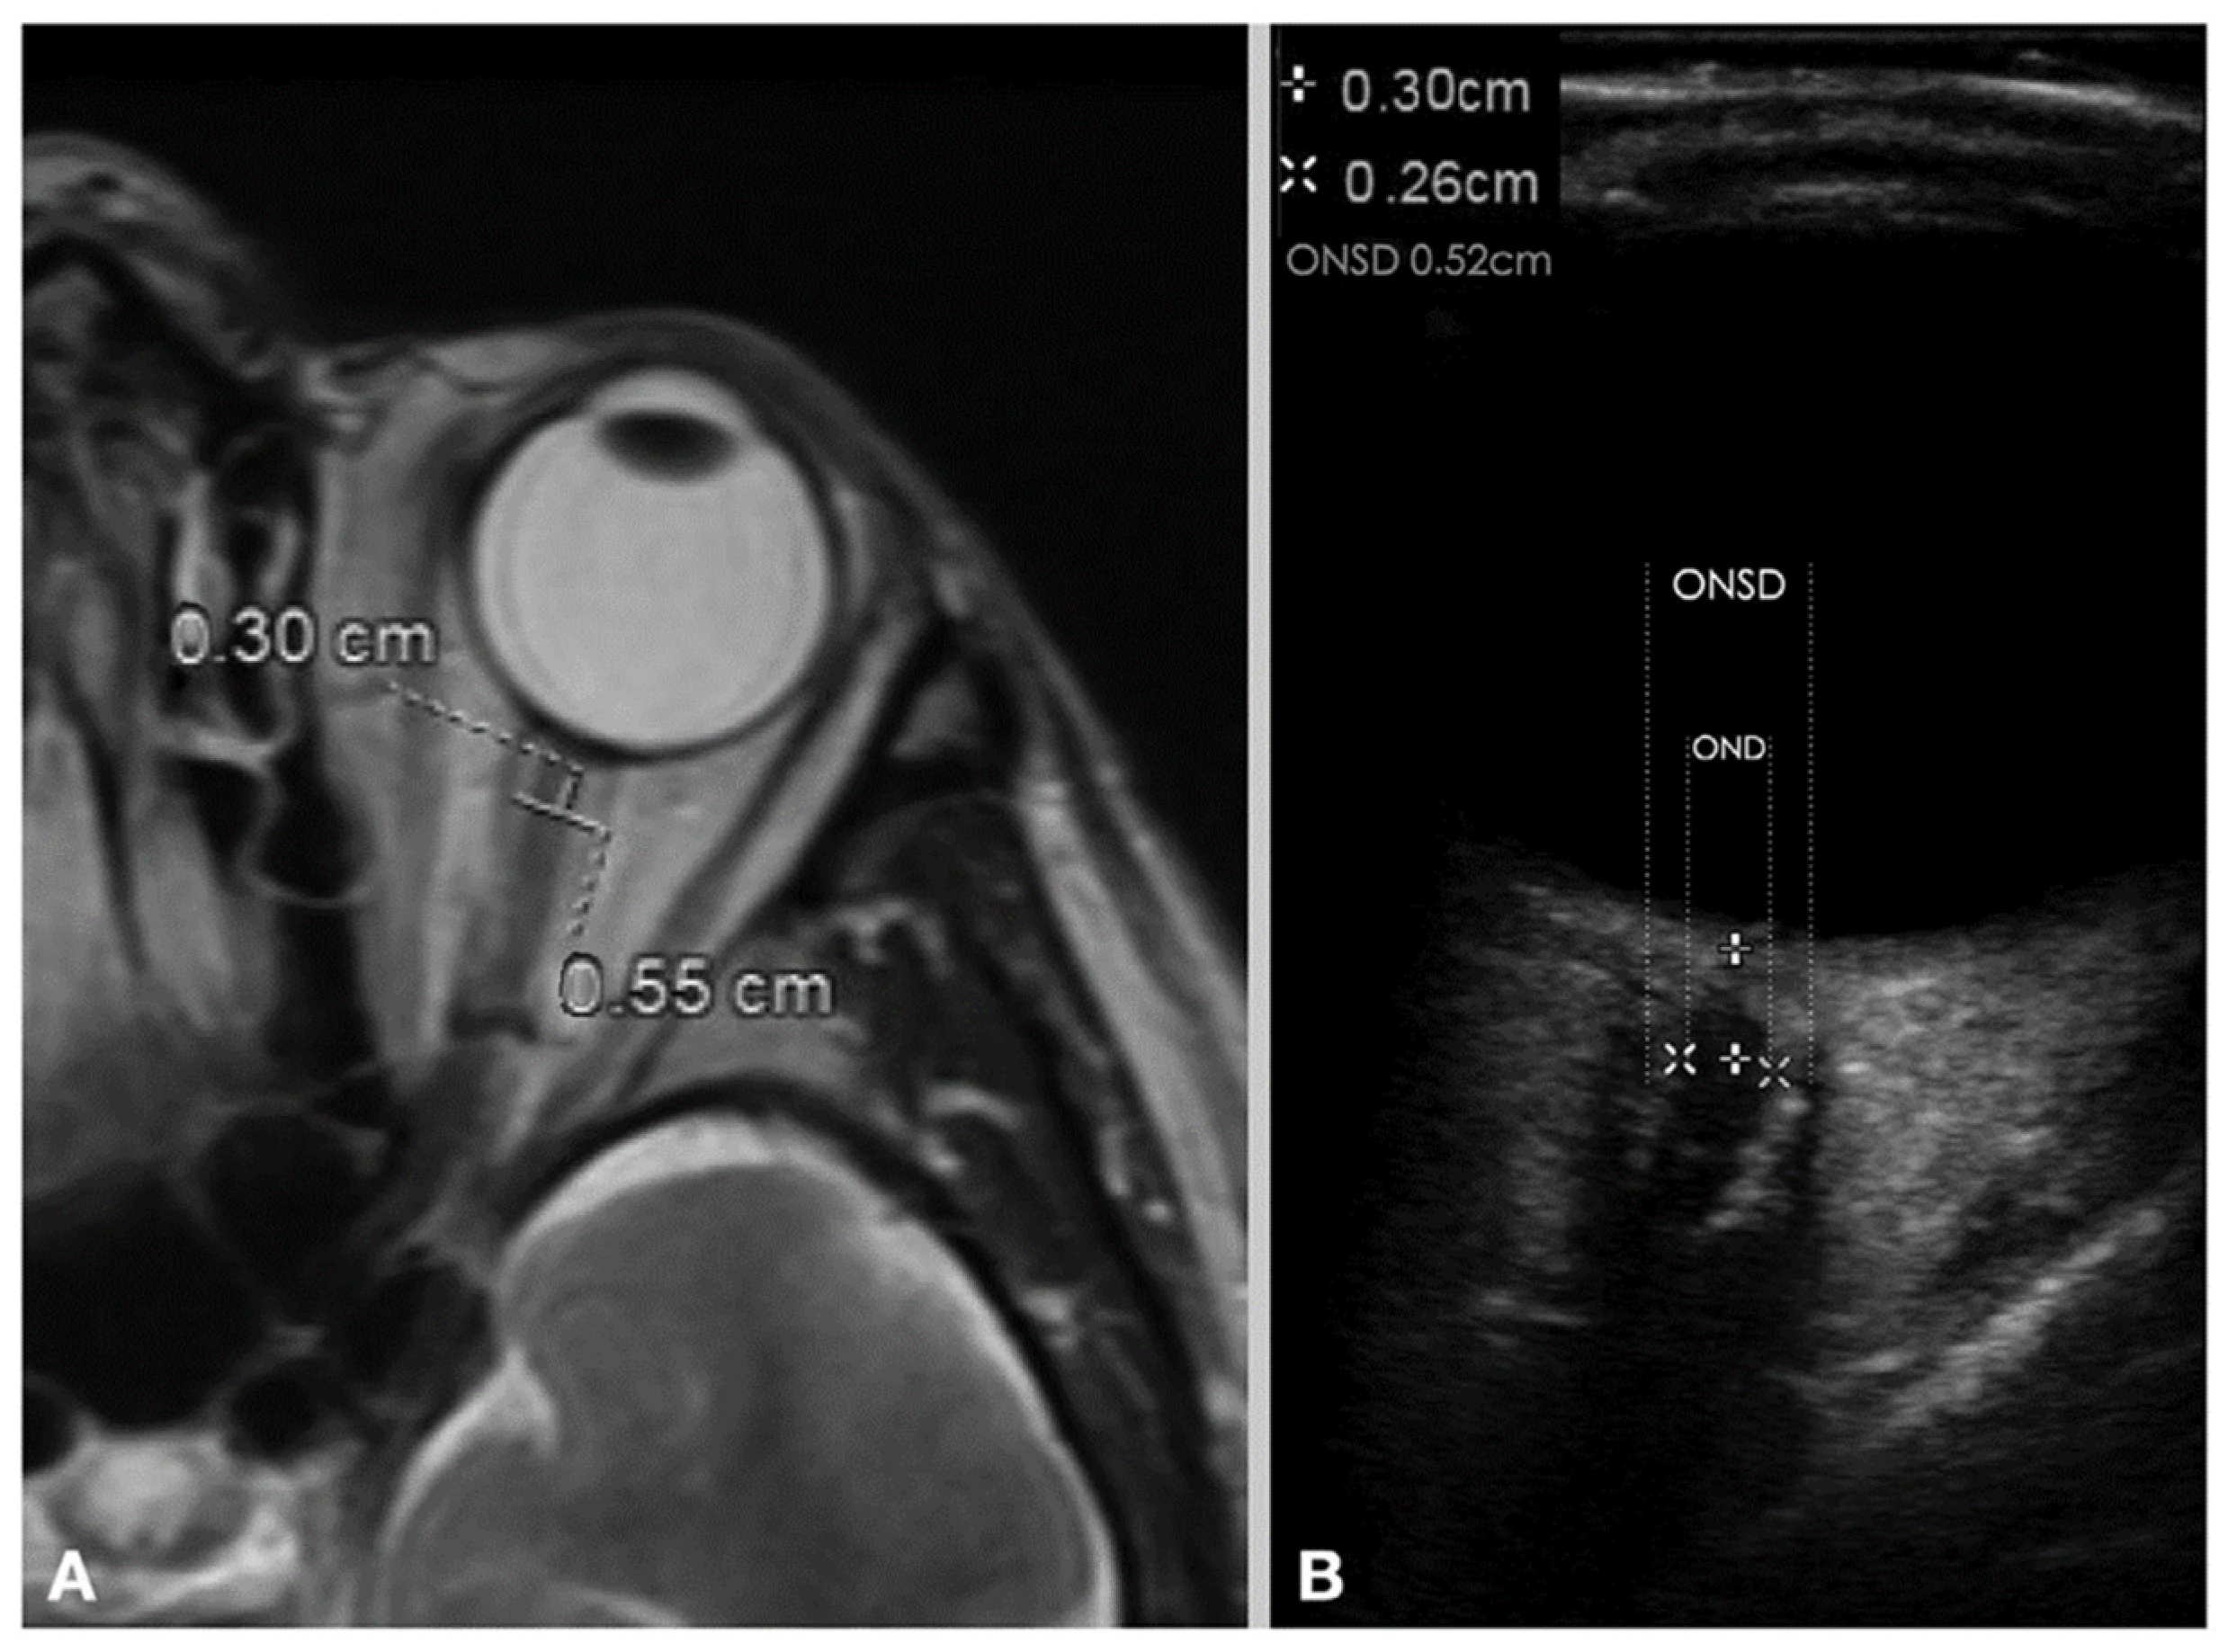

- Shokoohi, H.; Pyle, M.; Kuhl, E.; Loesche, M.A.; Goyal, A.; LeSaux, M.A.; Boniface, K.S.; Taheri, M.R. Optic Nerve Sheath Diameter Measured by Point-of-Care Ultrasound and MRI. J. Neuroimaging 2020, 30, 793–799. [Google Scholar] [CrossRef]

- Kim, D.Y.; Kim, S.Y.; Hong, D.Y.; Sung, B.Y.; Lee, S.; Paik, J.H.; Jung, H.M. Comparison of ultrasonography and computed tomography for measuring optic nerve sheath diameter for the detection of elevated intracranial pressure. Clin. Neurol. Neurosurg. 2021, 204, 106609. [Google Scholar] [CrossRef] [PubMed]